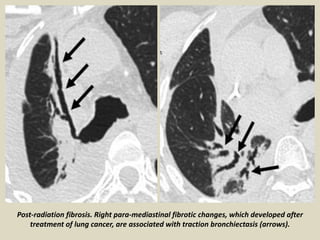

Post-radiation fibrosis. Right para-mediastinal fibrotic changes, which developed after

treatment of lung cancer, are associated with traction bronchiectasis (arrows).